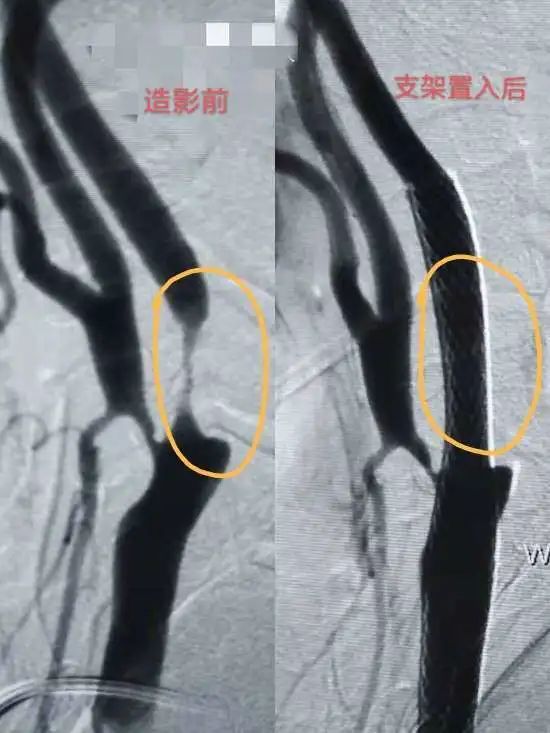

脑血管造影检查是将含碘造影剂注入到动脉,使血管显影,快速连续摄片,根据血管显影的形态和部位来诊断脑血管病的方法。脑血管造影由于给药部位不同,临床上分颈动脉造影、椎动脉造影、全脑造影和静脉窦造影等。

脑血管造影既可以显示血管本身的形态改变,如扩张、畸形、痉挛、狭窄、梗塞、出血等,又可根据血管位置的变化,确定有无占位。因此,它对诊断颅内血管本身的病变具有特殊意义。

在脑血管病诊断治疗方面有较高水平,擅长脑出血微创血肿清除、全脑血管造影、脑梗塞超早期动脉取栓、颅内外脑血管狭窄支架置入、颅内动脉瘤栓塞等神经介入治疗。